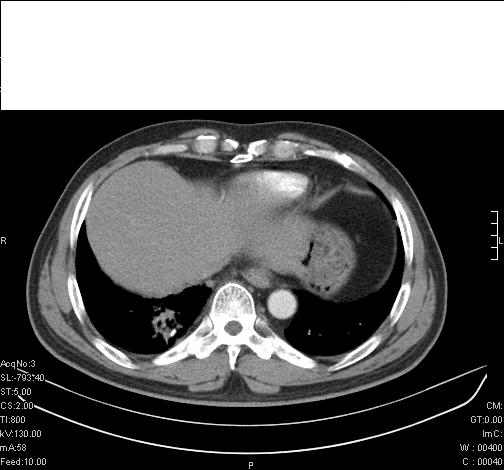

标题: CT6685:右肺阻塞性炎症,增强CT。

前几天,发了患者的平扫片,患者抗炎一周后增强扫描。右中叶病灶吸收明显,但下叶病灶未见明显吸收。右肺门可见结节影,看来凶多吉少

右肺下叶支气管管腔狭窄,管壁增厚,右下肺见斑片状高密度影,考虑右侧肺门中心肺癌伴阻塞性肺炎

右肺下叶支气管壁不规则增厚,右肺下叶有斑片状影分布。考虑右肺中央型肺癌伴右肺下叶阻塞性改变。建议支纤镜检查。平扫比增强较好显示了病变情况。

右主支气管狭窄,管壁增厚。考虑右中心性肺ca伴阻塞性肺炎。

既然抗炎治疗有效,可继续治疗;右肺下叶支气管管腔狭窄,管壁增厚,右下肺见斑片状高密度影,右侧主支气管后见结节影(淋巴结?),肺癌不能排出。